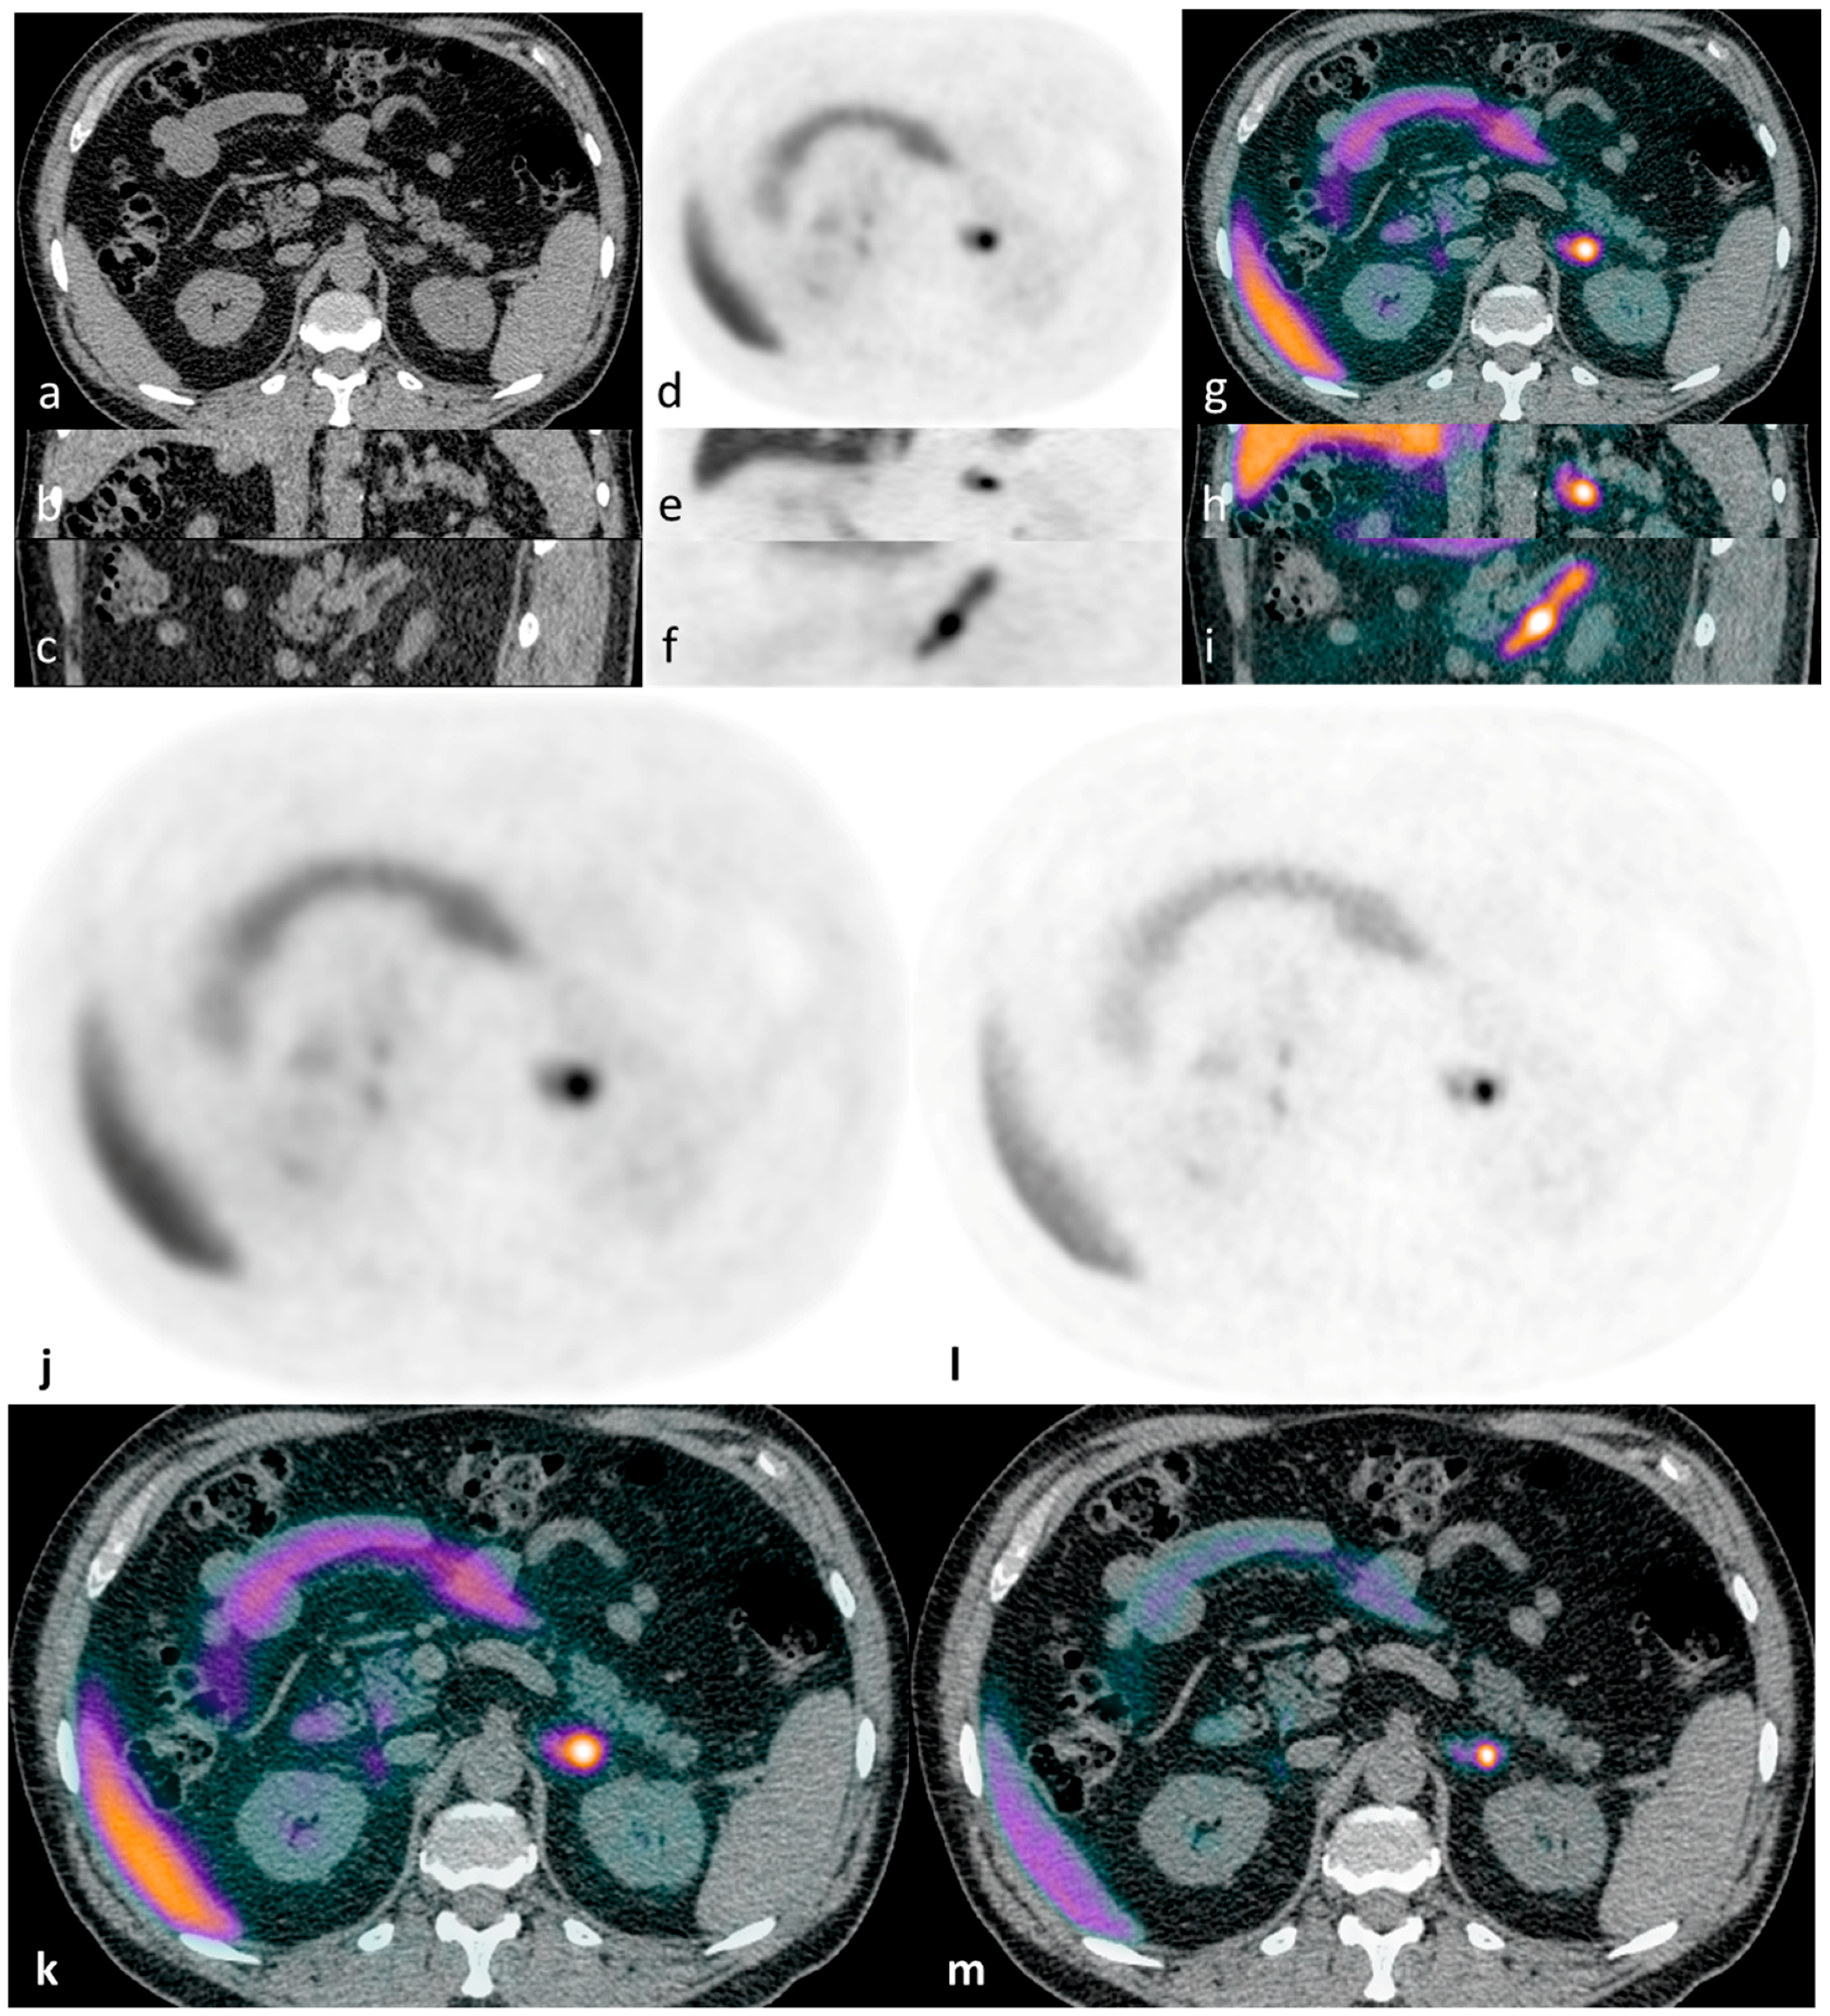

Figure 1.

Illustrative case 1: A 65-year-old man with a ten-year history of hypertension and hypokalaemia, requiring multiple agents for blood pressure control (including eplerenone) and oral potassium supplementation, was diagnosed with primary aldosteronism. CT demonstrated a lipid-poor 12 mm left adrenal nodule - displayed in axial, coronal and sagittal planes (a–c). 11C-metomidate PET-CT [(d–f) (PET) and (g–i) (PET-CT)] confirmed increased tracer uptake in the left adrenal nodule. The patient underwent laparoscopic left adrenalectomy, with subsequent histology confirming a classical Conn’s adenoma. Post-operatively, he had complete resolution of his hyperaldosteronism with excellent blood pressure control on progressive down-titrating medications (currently two agents with further weaning planned), and with no requirement for supplemental potassium at four-month follow-up. For comparison, axial PET/PET-CT images are shown as reconstructed via “time-of-flight” (TOF) iterative algorithms: without (j,k) and with resolution modeling (SharpIR) (l,m).